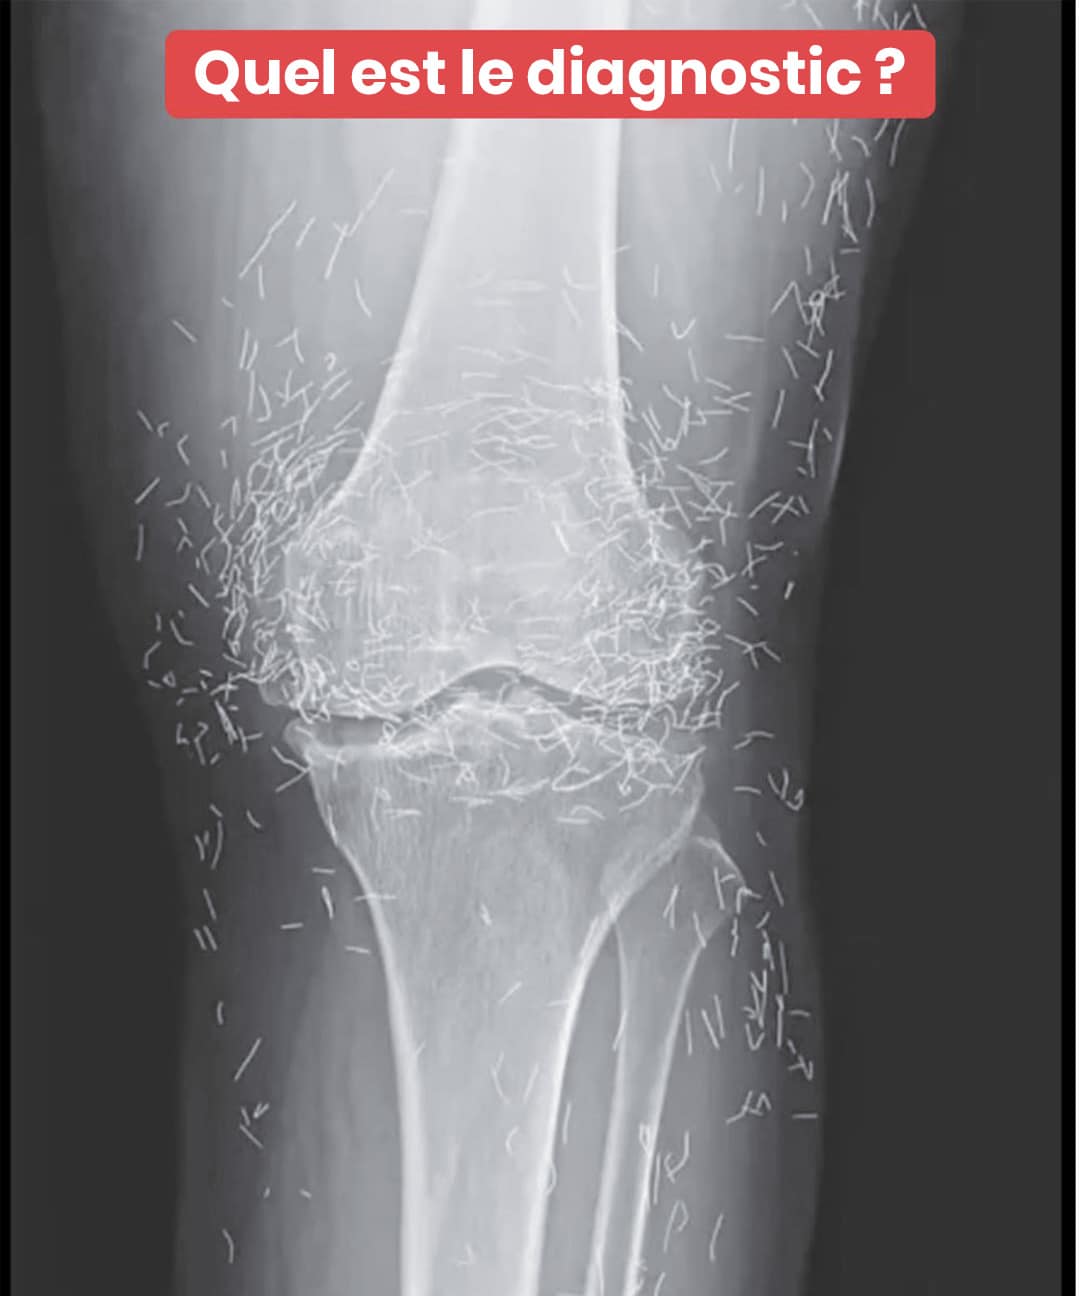

Une patiente découvre un trésor insoupçonné dans ses genoux grâce à une radiographie

Une simple radio des genoux a révélé une surprenante découverte chez une sexagénaire : des centaines de micro-aiguilles en or disséminées dans ses articulations. Cette révélation médicale met en lumière une pratique thérapeutique méconnue en Occident mais répandue en Asie. Plongée dans une aventure où médecine moderne et traditions ancestrales se rencontrent de façon spectaculaire.

C’est à l’occasion d’un examen d’imagerie médicale routinier que les praticiens ont observé, stupéfaits, la présence de centaines de petites aiguilles scintillantes réparties autour de ses articulations du genou. Une véritable énigme clinique qui a provoqué autant de fascination que de circonspection. Car si l’or présente une excellente tolérance biologique, la persistance d’éléments étrangers dans l’organisme n’est jamais dénuée de conséquences.

Selon des experts en radiologie, ces implants métalliques peuvent occulter certaines structures anatomiques sur les clichés radiologiques, compliquant ainsi le dépistage d’autres affections. Plus préoccupant encore : ils représentent une contre-indication sérieuse à l’IRM, puisque le risque de migration des aiguilles sous l’effet des champs magnétiques existe bel et bien, avec un potentiel de lésions tissulaires.